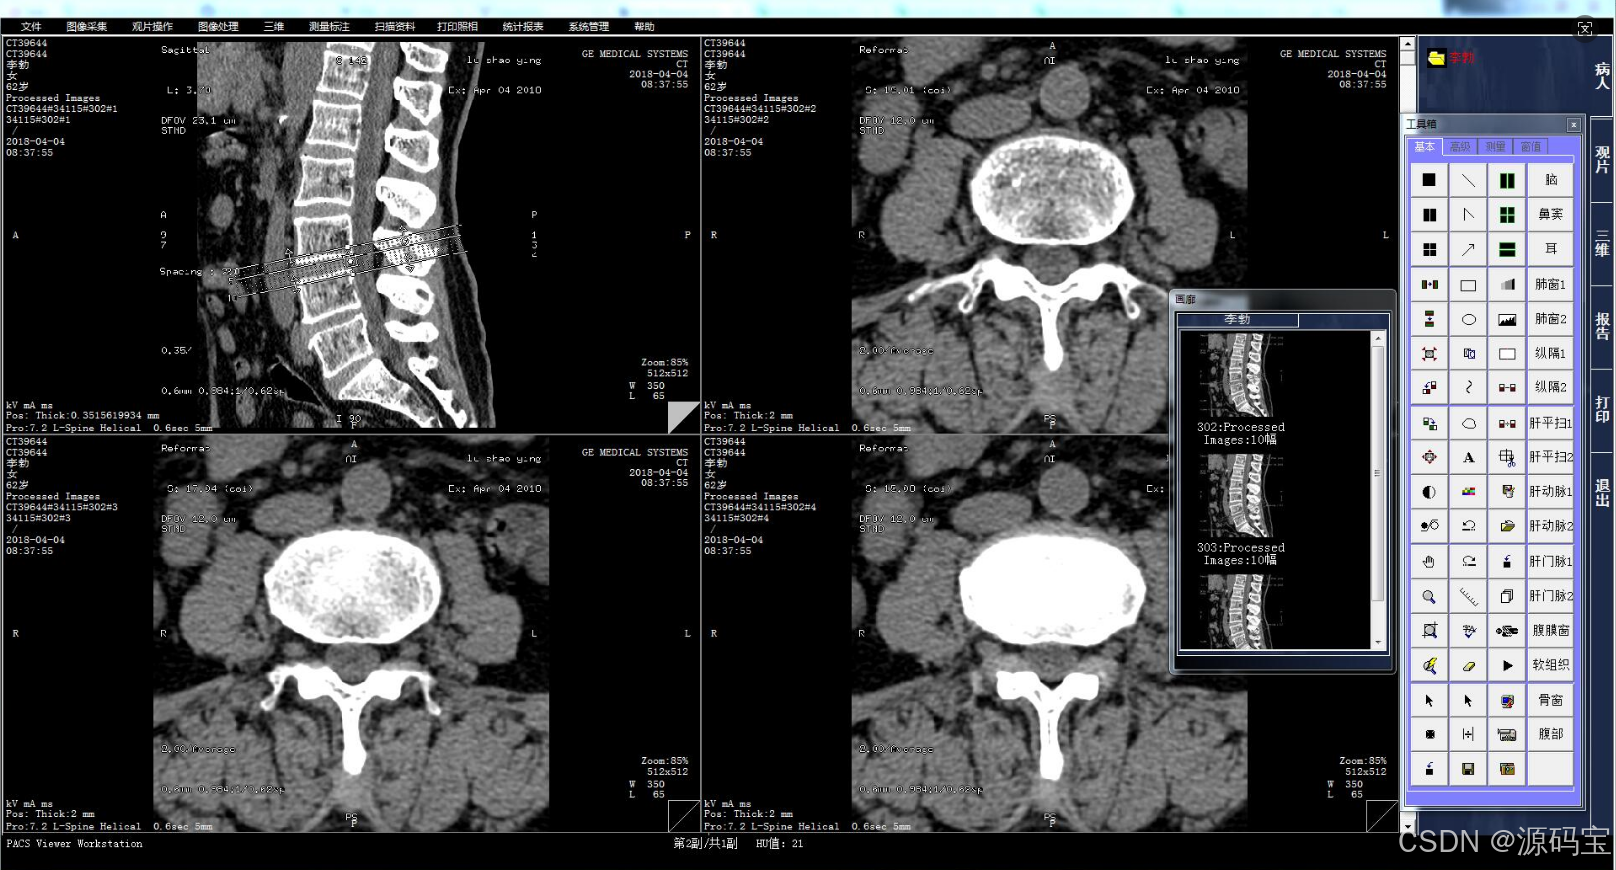

3、浏览图像

搜索到病人的影像信息后,可以在PACS系统中浏览和查看这些影像。系统会自动将病人的影像分成多个部位,可以根据需要选择浏览。

4、标记和测量

在查看影像时,可以使用系统提供的标记和测量工具对病人的影像进行标记和测量,以便更好地分析和诊断。